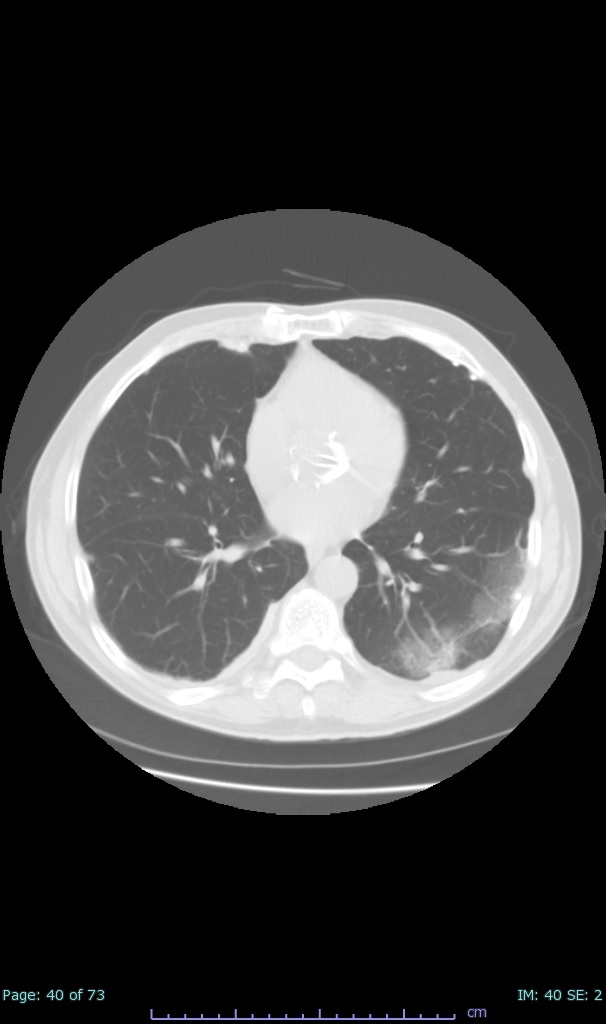

- 100% subpleural involvement, 33% + centrolobular involvement

- 40% even apical/basilar, 27% basilar dom, 5% mid dom. 1/17